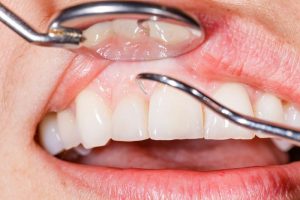

There aren’t many cosmetic or restorative dental treatments that can fix several of the most common dental problems at the same time. Whether you want whiter teeth, you need …